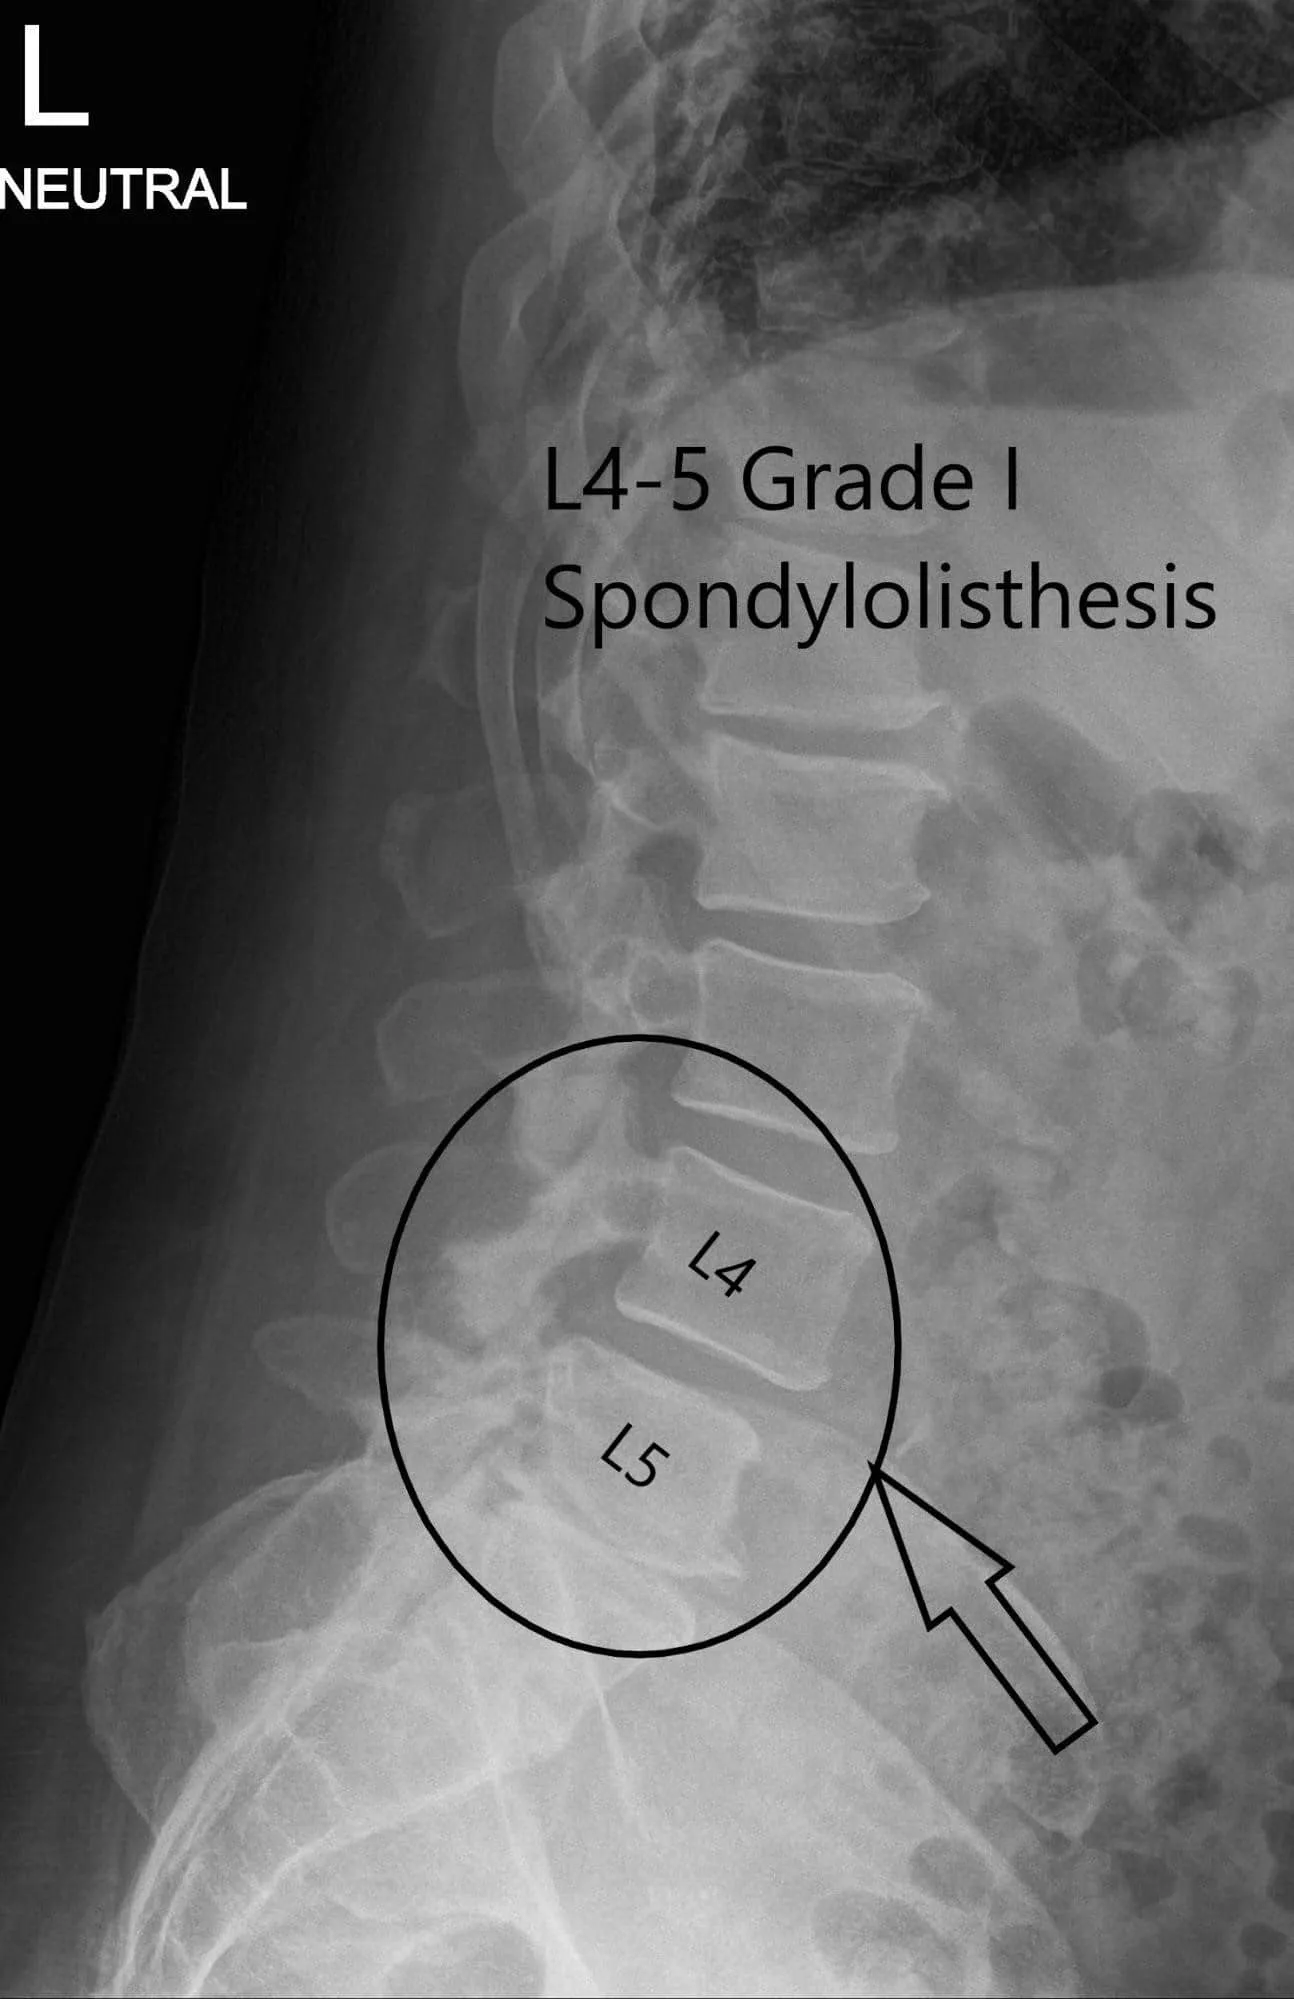

X-ray of the lumbar spine was reviewed with the patient. The X-ray revealed severe degenerative changes at L5-S1 and 5 mm anterolisthesis at L4-5.

Preoperative X-ray LS spine in AP and Lateral Views.